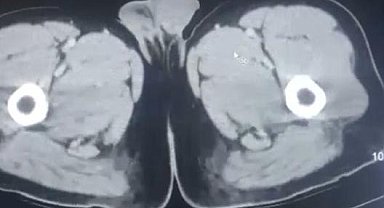

Midelerinden uyuşturucu çıkan İranlı 3 şüpheli, tutuklandı